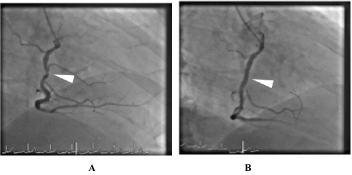

A 78-year-old male, ex-smoker, with a history of hypertension and hyperlipidemia presented with a one-month duration of worsening angina on exertion. Standard 12 L ECG showed sinus rhythm with early repolarization pattern in the anterolateral leads. Coronary angiography showed minor luminal irregularities in the left coronary vessels (Figure 1 A & B) while the RCA showed high grade non-thrombotic 90% lesion in its mid segment (Figure 2A arrow) followed by another high grade 90% stenosis in the RPDA branch (Figure 2B). A small calibre acute marginal branch (AMB) with an 80% ostial stenosis was noted to take off from the diseased mid RCA segment (Figure 2A arrowhead). Ad hoc percutaneous coronary intervention (PCI) of both the RPDA and mid RCA was carried out.

Figure 1. A. LAD and B. Non-dominant LCx, both vessels with minor irregularities